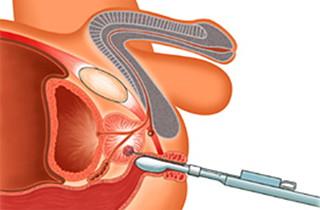

- 前立腺と直腸の間の隙間に注射針を挿入する操作を観察できるように、超音波プローブを挿入します(図:注入前)。

- 肛門開口部より2cm上部の皮膚から注射針を挿入。超音波を見ながら、直腸尿道筋を貫通し、前部直腸壁と前立腺の間の直腸周囲脂肪組織に達するように注射針を操作します。

- 注射針の位置を超音波画像で観察し、針先が直腸周囲脂肪組織の中にあることを確認し、生理食塩水を少量注入して空間を作成。その後にSpaceOAR®ハイドロゲルを前立腺と直腸壁の間(Denonvilliers筋膜 (腹膜前立腺筋膜))と直腸前壁の間)にスムーズに連続注入します(図:注入後)。